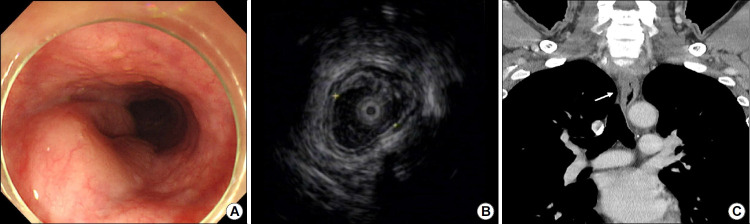

The gastrointestinal tract is the most common extranodal site for lymphomas, and mucosa-associated lymphoid tissue lymphoma is the second most common histological lymphoma subtype. However, primary esophageal mucosa-associated lymphoid tissue lymphomas are extremely rare. Few such cases are documented, and the reports demonstrate inconsistent diagnostic and therapeutic strategies. Herein, a 54-year-old man was referred to our hospital for treatment of dysphagia. Esophagogastroduodenoscopy revealed a large, horseshoe-shaped subepithelial mass in the upper esophagus. Endoscopic ultrasonography and computed tomography revealed that the mass was well-demarcated and confined to the muscularis mucosa, with no abnormalities in other organs or lymph nodes. The mass was presumptively diagnosed as benign, and the patient underwent endoscopic mucosal dissection for pathological confirmation and symptom relief. Pathological examination of the dissection specimen revealed that it was a primary esophageal mucosa-associated lymphoid tissue lymphoma. As the patient had an elevated immunoglobulin G level and Helicobacter pylori infection, we administered adjuvant eradication therapy. The patient remains under surveillance and is free of lymphoma recurrence 36 months postoperatively. This case report demonstrates that endoscopic resection and H. pylori eradication are effective treatment strategies for early-stage esophageal mucosa-associated lymphoid tissue lymphoma.